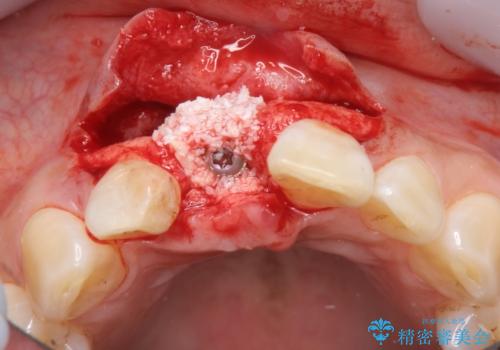

審美的・機能的に良好な位置に埋入するには、骨量が十分ではなかったため骨の造成を併用したインプラント埋入外科手術を行います。

前歯のインプラントを審美的に仕上げるには、インプラント周囲に十分な骨の量と厚みのある歯肉、そして埋入位置の精密な位置付けが重要です。